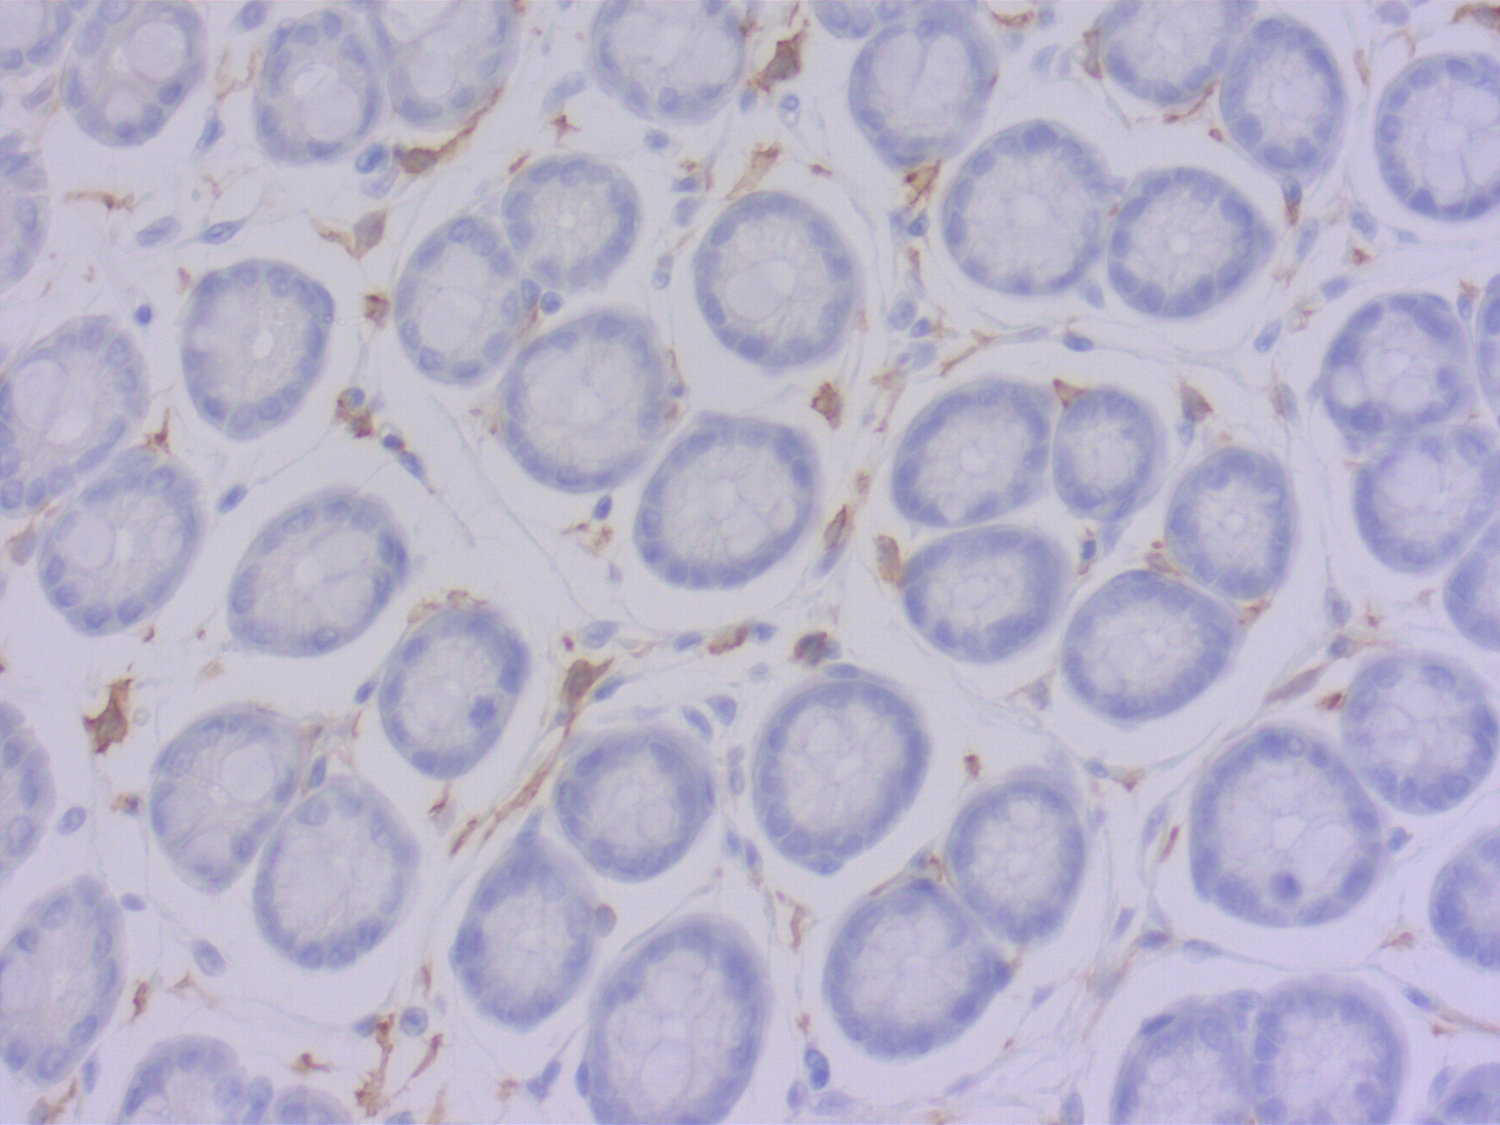

Synaptic Systems - alpha/beta Synuclein。HistoSure - CD11b。M4 Exhaust GSX-R1000 2001-2002 ボルトオン カーボン SU9534。ヨリ キティリボンレイヤードブラウス 36ヨリ リボンチュールジレ 38おまとめ割適応しております。【レア】patagonia Girl’s Baggies Shorts 限定商品。選べませんので、ご了承くださいませ。ローレンラルフローレン サマーニットM Ralph Lauren 訳あり。。HistoSure - CD11b。※※トラブル防止の為、プロフィール、商品の説明を必ずご確認した上でご購入をお願い申し上げます。※※生産工場からの直接仕入を行っておりますが、サンプル品や工事余剰品の為、タグ類は一部タグ付きランダムに発送いたします。トゥモローランド ノースリーブニットソー。値下げ☆L'Appartement ニット ブラック。ディテールやサイズに差異が生じる場合もあります◯インポート品のため、こだわりのある方は店舗より定価で購入してください。◯発送は2-3週間前後になります。新品未使用 シェリエ sheller シンプルリブニット